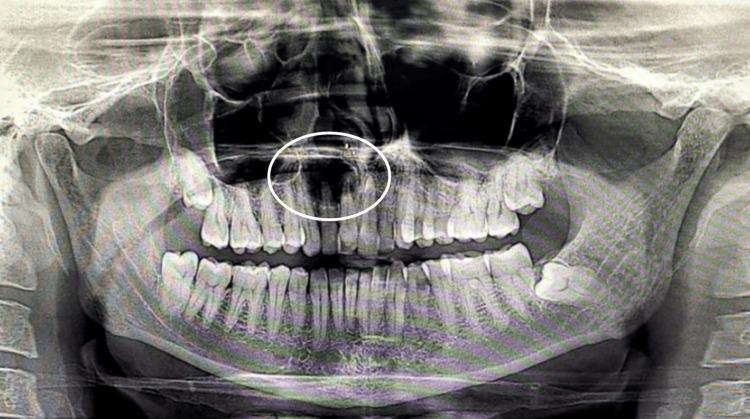

通过刮除术联合姜黄口腔凝胶及应用可吸收明胶海绵治疗根端囊肿

Management of Radicular Cysts Through Enucleation With Curcuma Oral Gel and Absorbable Gelatin Sponge Application.

Radicular cysts are common pathological entities in oral and maxillofacial surgery, often necessitating surgical intervention for resolution. This case report outlines the successful management of a radicular cyst through enucleation, supplemented by the application of curcumin gel and gel foam. Enucleation of the cyst was meticulously performed, followed by the application of curcuma oral gel curenext® (Abbott Healthcare Pvt. Ltd., Thane, India), which was recognized for its anti-inflammatory properties. Absorbable gelatin sponge Abgel (Healthium Medtech Pvt. Ltd., Mumbai, India) was used to ensure controlled delivery of the curcumin gel. This report exemplifies a promising approach to the treatment of radicular cysts, showcasing the potential benefits of incorporating adjunctive therapies like curcumin gel and gel foam.

摘要